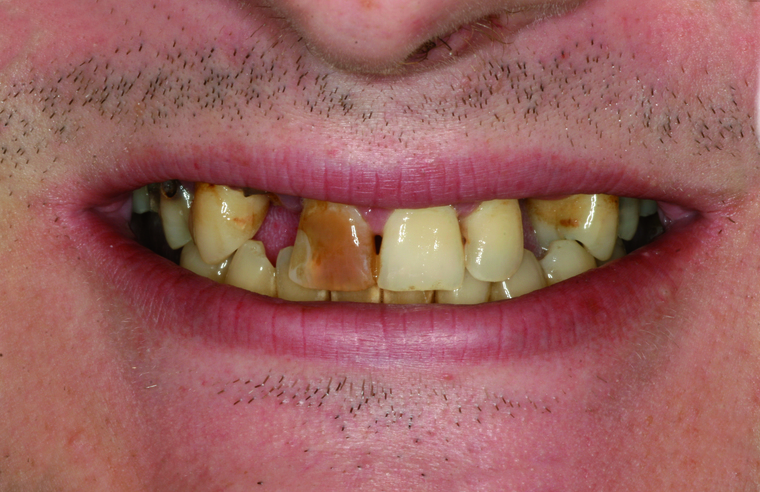

Viele Kunden die zu uns nach Salzburg kommen benötigen eine Generalsanierung der Zähne. Gründe dafür sind Zahnarztangst, Zeitmangel und schlechte Erfahrungen in der Kindheit. Unser Konzept ist genau auf diese umfangreichen Fälle abgestimmt:

Bei einer Generalsanierung müssen alle zahnmedizinischen Bereich in Betracht gezogen werden, dies beginnt bei der Aufklärung und Prophylaxe, gefolgt von Zahnfleischbehandlungen und Kariestherapie, eventuellen Zahnentfernungen, Knochenaufbauten und wird durch ästhetischen Zahnersatz abgeschlossen. Unser Recall-System hält die erreichte Zahnsanierung über lange Jahre stabil.